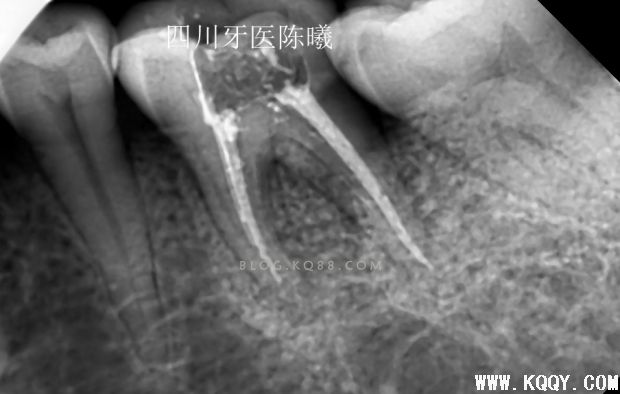

试尖完发现近中稍欠,远中颊根部到位,于是用20#25#K挫稍微挫了下根尖3分之1,远颊根挫时病人告知有疼痛,依然没有重视,在冲洗的时候发现少许没有去除干净的氢氧化钙糊剂从根管内溢出,又是一个问题,这下觉得应该到位了,那就充填吧,于是用试尖的牙胶尖号数充填,结果如下

从这3张片子上可以看出近远中都有超填,唉,重来吧!(发博客都一波三折,这都第四次编辑了,不容易啊)跟病人说清楚情况取得同意后,准备重新充填,但是这个时候不知道近远中超填的是颊根还是舌根,又一个问题,只有想办法,我去掉近远中颊根充填物后照片(远中充填得很密合,废好大功夫才取出来)

可以看出在取出近远中颊根充填物后,远中依然超填,说明远中超填的是舌根,然后觉得近中舌根充填锥度也不连续,干脆全部取出重新做!